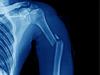

Deformācijas piemērus var aplūkot tabulā:

spiede